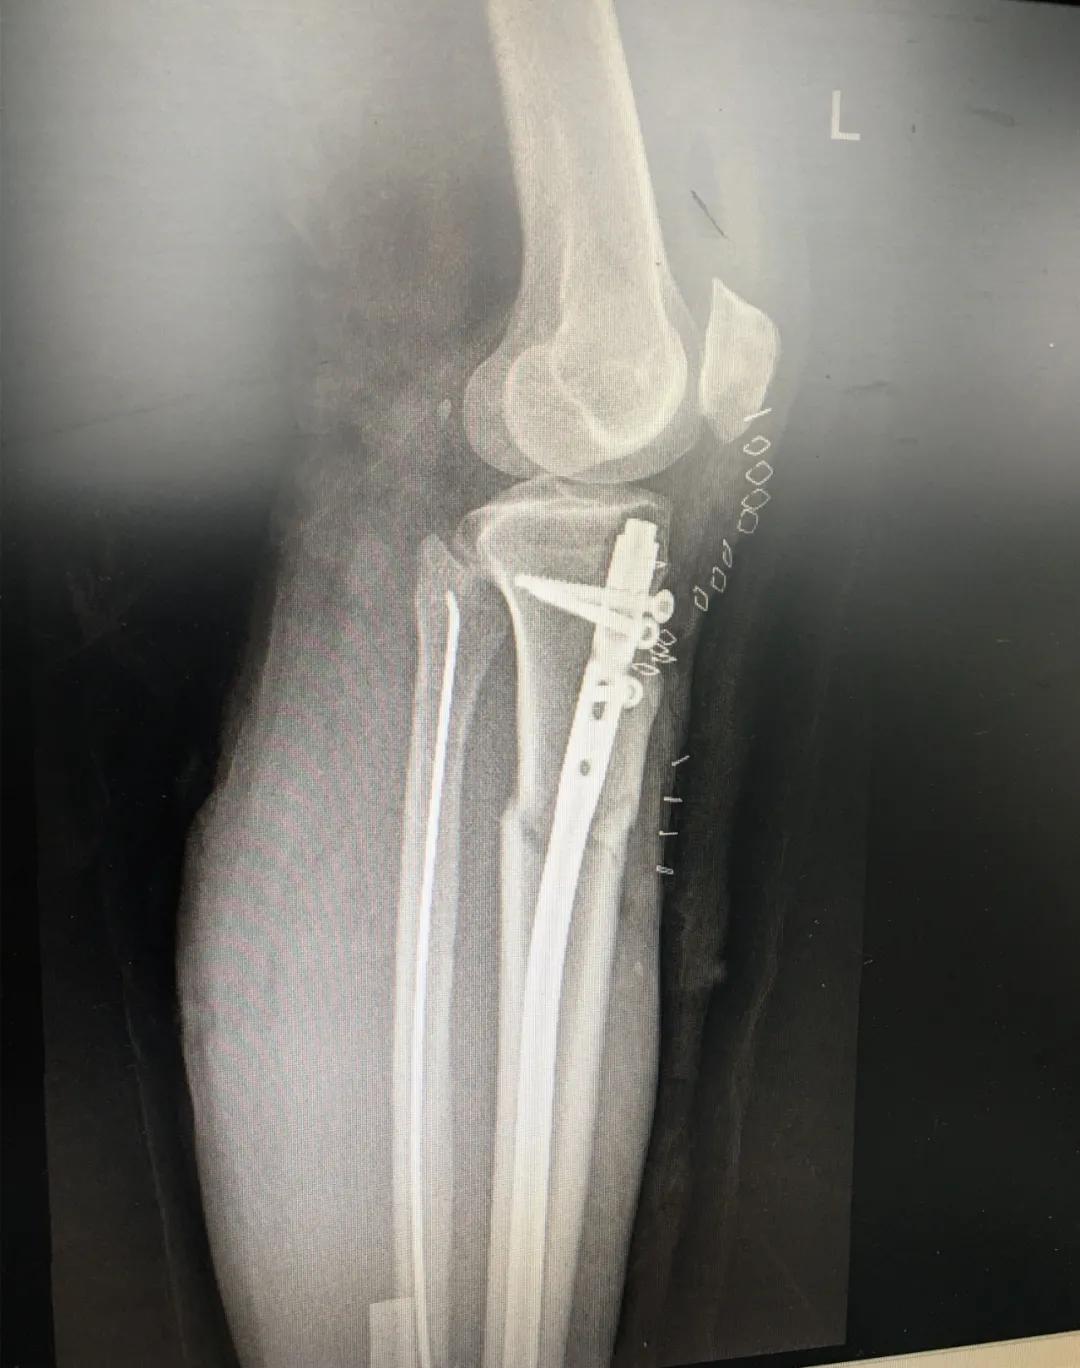

为患者实施的骨折微创复位固定技术是创伤骨科的特色技术。相较传统手术需要20公分的切口,微创手术只需要3公分左右。闭合复位髓内钉固定技术、经皮插板内固定技术(mippo技术)、闭合复位空心螺钉固定技术等一系列的微创复位固定技术,具有切口小、出血少、创伤小、愈合快、疤痕小等优点,骨折术后并发症明显降低,患者还可以早期负重功能锻炼。

另一位患者朱先生因车祸导致了右胫腓骨骨折,同样的小腿三段骨折,实施了微创闭合复位髓内钉固定术后,目前已经逐步进行康复功能锻炼。